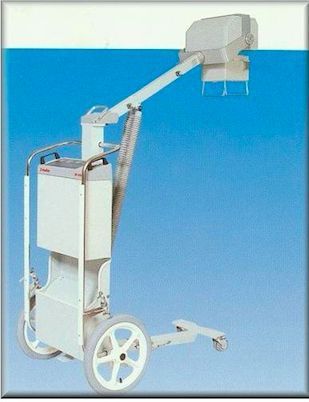

Del Medical Dynarad HF 110 Portable X-Ray